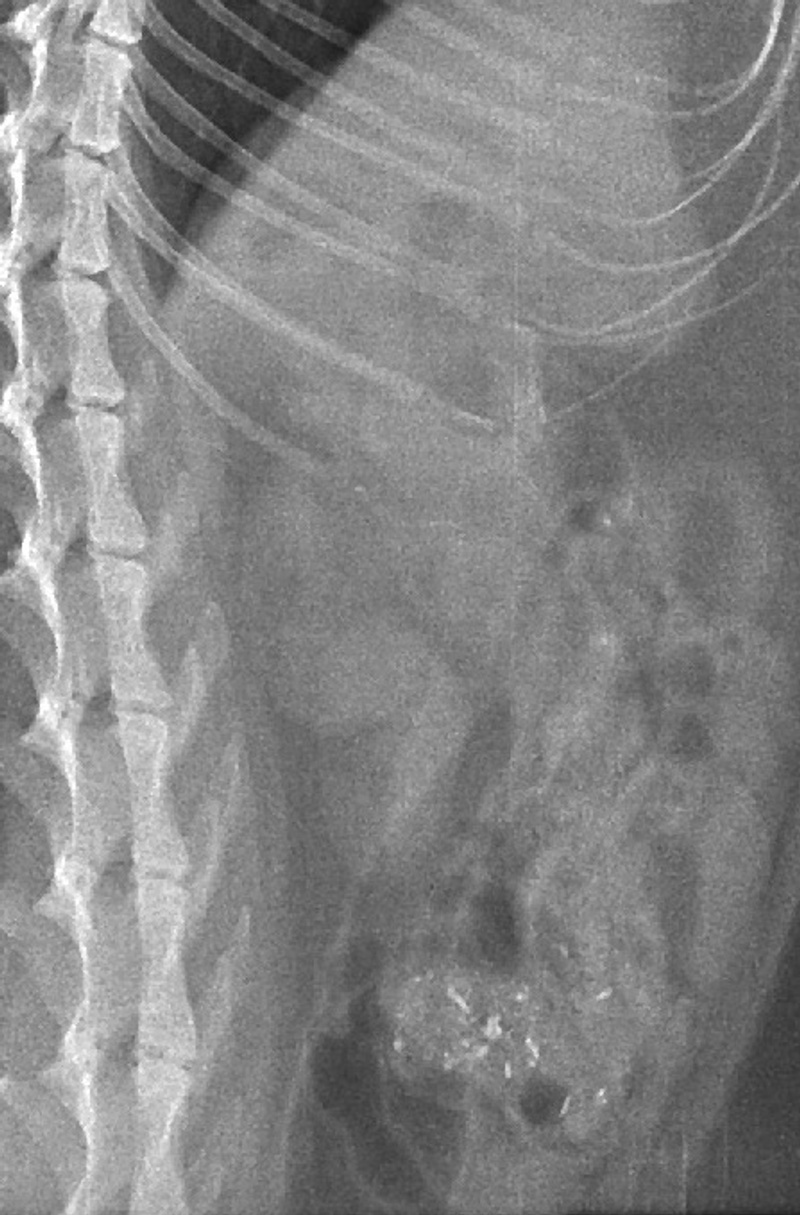

Первичный осмотр показал кишечную непроходимость/предмет в кишечнике, сказали надо резать... В коматозном состоянии я согласилась, однако позже мне позвонили, сказали, что операция отменяется, тк у кота обнаружили шишку на шее, которая, по их версии, мешала глотать, сдавливала трахею, отсюда и рвота. Шишку прокололи, оттуда вылилось немного жидкости, по их словам, состоящую из двухядерных (раковых) клеток. Посоветовали разобраться с кишеником, а потом обследовать шишку путем КТ.

Однако, коту стало хуже, отказывался от еды, начали желтеть ушки и кожа...В той же ветеринарке, развели руками, сказали, что отказывает печень - усыпляйте...